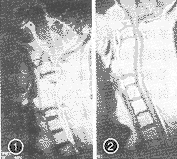

患者男,56岁,13年前因“四肢麻木行走无力二便困难1年”,以CSM收入院。CT示C3/4、C4/5、C5/6间盘突出并椎管狭窄,行C3/6开槽减压植骨术,术后症状逐渐好转,1年后能从事一般体力劳动。首次手术后11年症状复发并逐渐加重,疗效评分降低至22分(40分评分法),CT及MRI检查均显示已融合的上下相邻节段间盘突出、黄韧带肥厚形成环状狭窄(图1)。局麻下行颈椎后路双开门椎管扩大成形术(图2),术后症状改善。

图1 第1次术后11年MRI示C2/3、C6/7间盘突出,黄韧带肥厚 图2 再次后路减压术后MRI示环状狭窄已解除